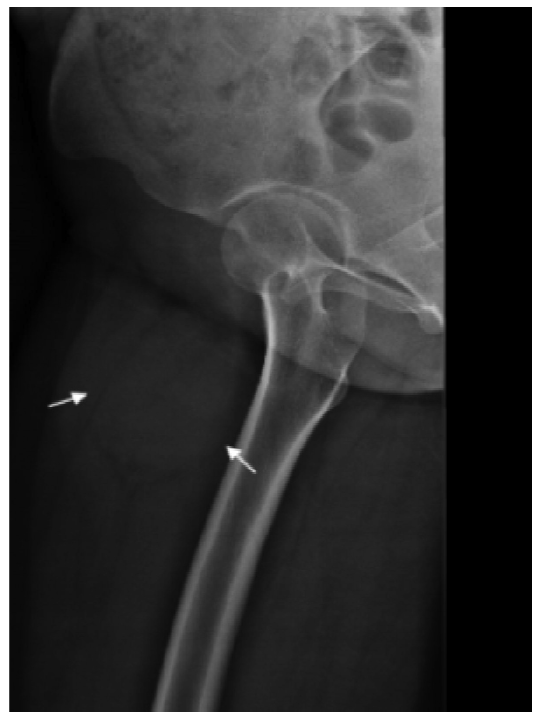

图2

病人女,23岁,右下肢软组织恶性PEComa,伴

TFE3

重排。X线平片显示软组织内团块状密度增高影,周围可见透亮影。